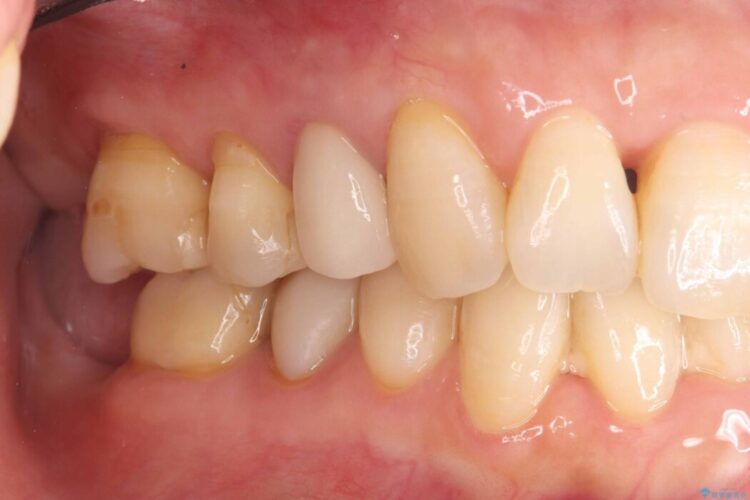

破折したセラミックインレーのやり替え

他院で装着されたセラミックインレー(MOD窩洞)が破折したとご来院されました。

歯の中央から両側にかけて大きく削られている(MOD窩洞)状態でした。

噛む力がかかることで、インレーでは負担に耐えきれず破折してしまったと考えられます。